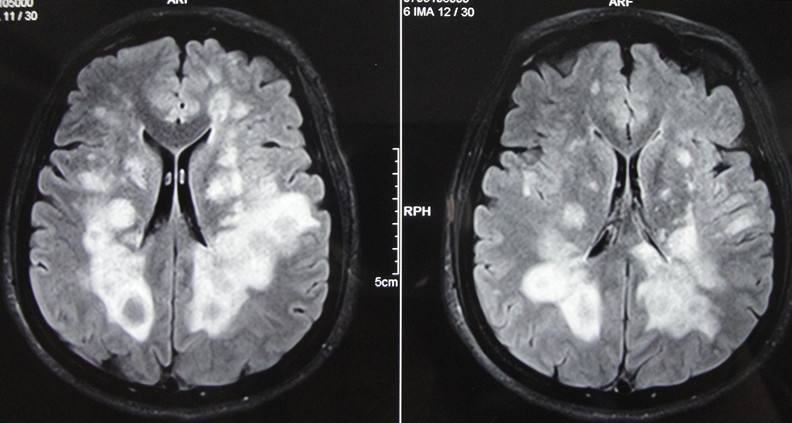

患者,男,李XX,41歲,家住本市,該患于入院前2年,無明顯誘因出現(xiàn)右側(cè)肢活動(dòng)不靈,表現(xiàn)為走路時(shí)腿拖拽,伴有言語不利,尚可與人交談,在“吉林大學(xué)第一醫(yī)院二部”行頭部MRI及腰椎穿刺檢查后診斷為“脫髓鞘病”,治療后好轉(zhuǎn)出院,20天前患者癥狀加重,并伴有左側(cè)肢活動(dòng)不靈,癥狀無緩解,未予任何治療來我院就診,病程中患者有視物雙影,飲食、睡眠尚可,尿便正常。查體:體溫36.5℃,脈搏71次/分,呼吸18次/分,血壓140/80mmHg,神志清楚,言語不利,查體合作,計(jì)算力、記憶力、定向力、理解力、判斷力正常,雙側(cè)額紋對(duì)稱,雙側(cè)瞳孔等大同圓,直徑約3.0mm,對(duì)光反射靈敏,雙眼各向運(yùn)動(dòng)正常,無眼球震顫,無鼻唇溝變淺,伸舌居中,懸雍垂居中,雙側(cè)咽反射靈敏,右側(cè)肢體肌力3級(jí),左側(cè)肢體肌力4級(jí),肌張力增高,膝腱反射亢進(jìn),雙側(cè)Babinski征(+),頸無抵抗 ,雙側(cè)Kernig征(-),昂伯士征(+),雙側(cè)肢體深、淺感覺未見異常,雙肺呼吸音清,心率71次/分,節(jié)律規(guī)整,各瓣膜聽診區(qū)未聞及雜音,腹平軟,無壓痛,肝脾肋下未觸及,雙下肢無浮腫。入院后行頭部、頸椎、胸椎MRI:脫髓鞘病病史: 雙側(cè)側(cè)腦室后角、下角旁、放射冠及半卵圓中心、胼胝體見片狀及團(tuán)塊狀異常信號(hào)影,T1WI呈低信號(hào),T2WI及FLAIR呈高信號(hào);各腦室、腦池大小形態(tài)未見明顯異常,中線結(jié)構(gòu)居中,矢狀面掃描示垂體大小形態(tài)正常。彌散成像腦質(zhì)未見明顯異常高信號(hào)影。頸椎生理曲度變直,部分椎體邊緣骨質(zhì)增生。C3/4、C4/5、C5/6間盤向后方局限性突入,硬膜囊前緣受壓。黃韌帶未見明顯增厚。頸髓未見明顯異常信號(hào)影。 胸椎生理曲度尚可,椎體骨質(zhì)結(jié)構(gòu)完整。各胸椎間盤未見明顯突出或膨出,黃韌帶無增厚。約T2、5、12椎體水平脊髓內(nèi)見條片狀長T2信號(hào)影。心電圖示:竇性心律,心率71次/分,大致正常心電圖。此次考慮患者脫髓鞘病復(fù)發(fā),經(jīng)過吉大一院劉群教授會(huì)診后,給予激素大劑量沖擊治療,病程中激素逐漸減量,經(jīng)過一個(gè)療程的治療,患者癥狀較前明顯好轉(zhuǎn),肢體活動(dòng)較前靈活,患者滿意的出了院。